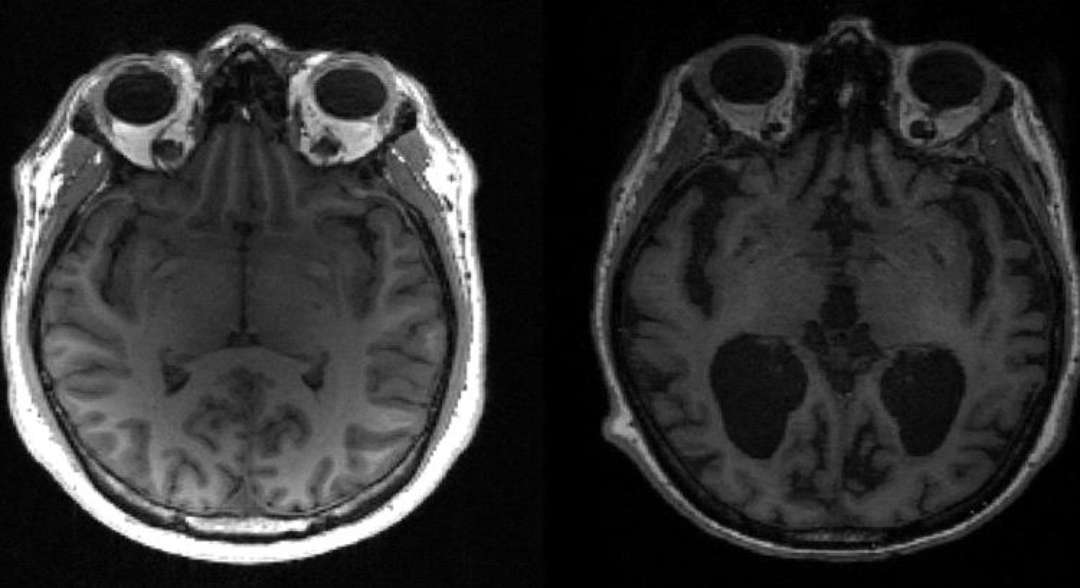

يقول العلماء إنهم حددوا شكلاً وراثياً جديداً لمرض ألزهايمر مما يبرز الحاجة الملحة لتطوير استراتيجيات علاجية ووقائية متخصصة.

وأفاد باحثون من الولايات المتحدة بأن معظم الأشخاص تقريباً الذين يحملون نسختين من الطفرة الجينية "أبوليبوبروتين ب 4" APOE4 [وتُعرف أيضاً باسم صميم البروتين الشحمي E 4]، المعروفة باسم متماثل الزيغوت homozygotes، من المرجح أن تظهر عليهم علامات المرض العصبي هذا.